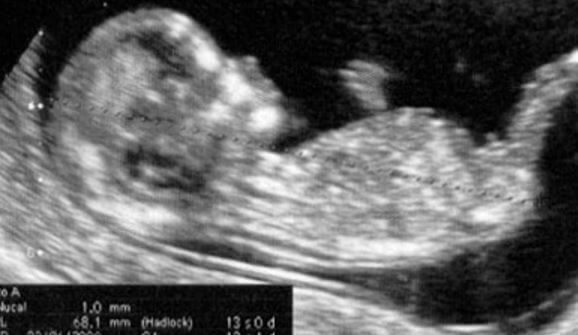

Na 13ª semana de gestação ainda se pode realizar, no caso de não ter sido realizada ainda, a ultrassonografia do final do primeiro trimestre. Esse é o último passo de uma série de exames que devemos fazer desde que sabemos que estamos grávidas. É o ponto em que se encerra a avaliação do primeiro trimestre. E podemos dizer que a parte mais difícil e angustiante (principalmente para uma mãe de primeira viagem) já passou.

De agora em diante, a fase dos exames médicos faz uma pausa, embora dure apenas um período curto. Precisam ser feitos, nesse intervalo, controles periódicos ou mensais para nos certificarmos de que o feto está se desenvolvendo corretamente e que a mãe também não está sofrendo nenhum tipo de problema.